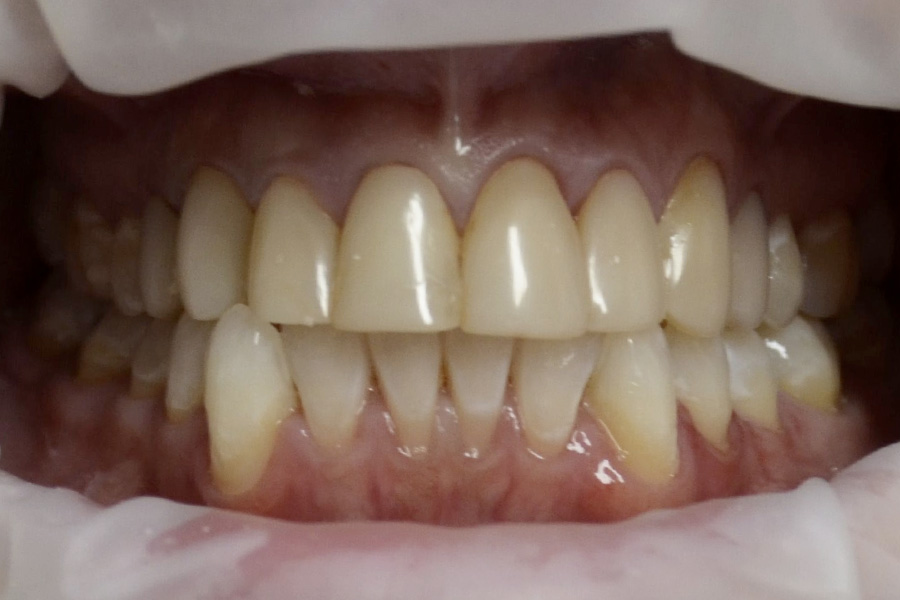

The following cases had Composite veneers for a few years.

They decided to have them replaced with ceramic veneers as the composite veneers appeared dull and required frequent repair. Minor correction of alignment was also performed while making ceramic veneers.